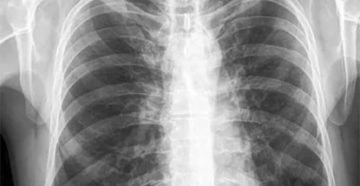

Метатуберкулезные изменения в легких: что это, причины, лечение Метатуберкулезные изменения в легких в большинстве…